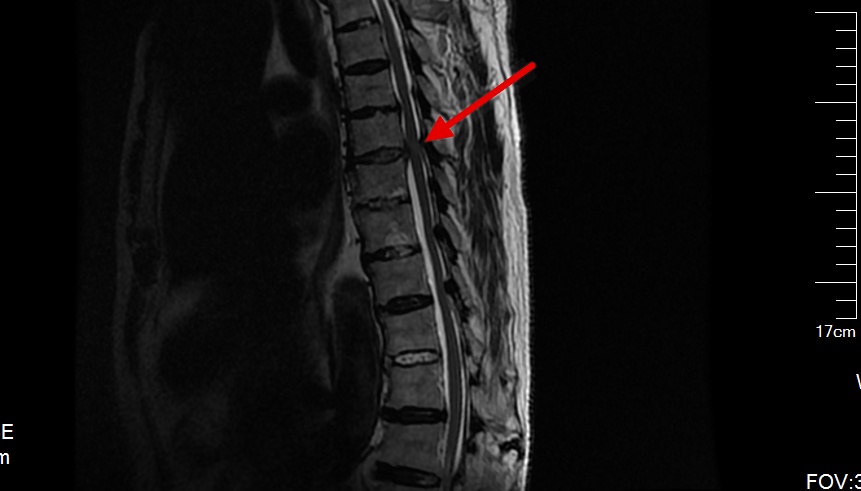

从术前的腰椎磁共振我们可以看到腰椎向下脱垂游离的巨大间盘突出,压迫右侧神经根,我们给她做了后路脊柱内镜下腰椎间盘摘除术。

术后第二天复查腰椎磁共振我们可以看到脱垂的间盘组织被完整的摘除,术后当即患者的症状就消失了,可谓立竿见影。